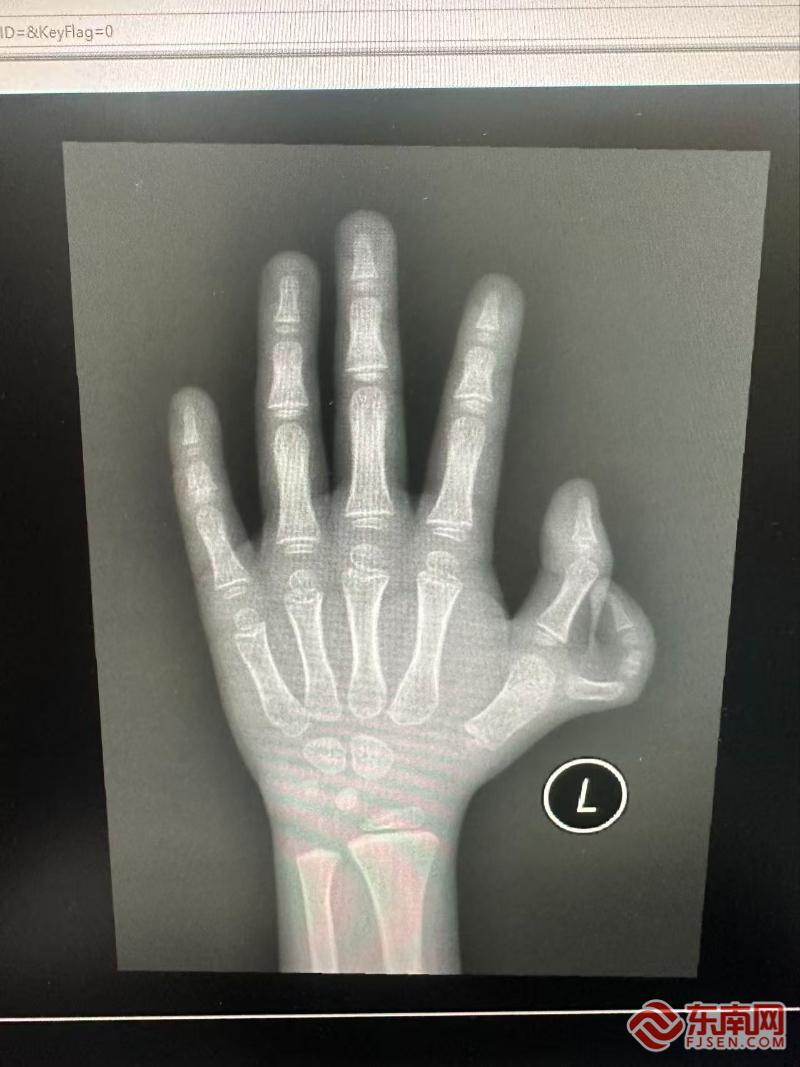

影像画面。闽东医院供图

东南网11月19日讯(本网记者 周涛 通讯员 林俊)“医生,您快帮帮我的孩子吧!”近日,在宁德市闽东医院创伤骨科、手显微外科诊室内,浩浩妈妈王女士哽咽求助。六岁的浩浩因左手多长出一根拇指,被小伙伴称为“六指怪物”,性格逐渐内向,甚至习惯将左手藏进口袋。经郭卫中主任医师确诊,浩浩患有“Wassel IV型拇指多指畸形”,需通过复杂手术实现功能重建。

郭卫中主任医师指出,该畸形并非简单切除多余指,而是需从骨骼、韧带、肌腱三维度修复。若仅切除,保留下来的拇指会因失去支撑而偏斜,影响握笔、抓取等精细功能。手术团队需在方寸之间“精雕细琢”,分离血管神经、切除多余指,并重建关节囊、矫正偏斜、调整肌腱张力,确保拇指稳定性和功能。